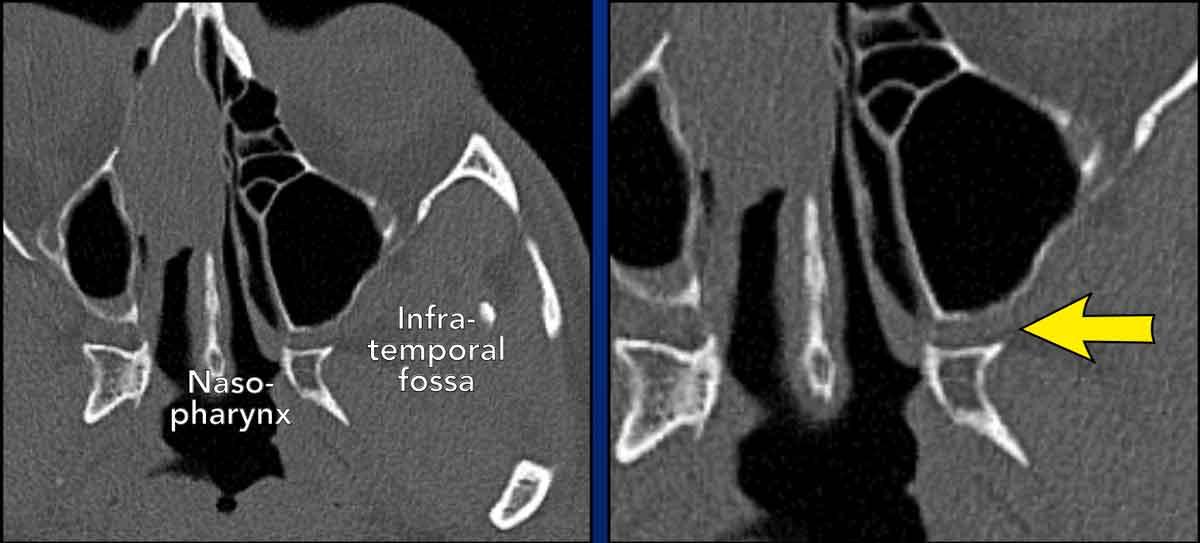

Hố chân bướm khẩu cái

Hố chân bướm khẩu cái là một khoang hình tháp ngược, chứa đầy mỡ, nằm ở mặt bên của hộp sọ, giữa hố thái dương dưới và vòm họng mũi.

Đây là một ngã tư thần kinh mạch máu quan trọng, kết nối hốc mắt, hốc mũi, vòm họng mũi, khoang miệng, hố thái dương dưới và hố sọ.

Do các kết nối này, hố chân bướm khẩu cái có thể đóng vai trò là đường dẫn cho sự lan rộng của các bệnh lý viêm nhiễm và tân sinh ở vùng đầu cổ.

Các hình ảnh này thuộc hai bệnh nhân khác nhau.

- Đây là bệnh nhân có ung thư biểu mô tế bào vảy xuất phát từ xoang hàm phải, xâm lấn vào hố chân bướm khẩu cái (mũi tên đỏ).

Lưu ý mô mỡ bình thường trong hố chân bướm khẩu cái bên trái (mũi tên vàng). - Đây là bệnh nhân nam 16 tuổi của chúng ta.

Lưu ý rằng hố không bị xâm lấn và tâm của tổn thương không nằm ở lỗ bướm khẩu cái và hố chân bướm khẩu cái.

Điều này khiến chẩn đoán ban đầu là u xơ mạch máu vị thành niên trở nên khó có khả năng.